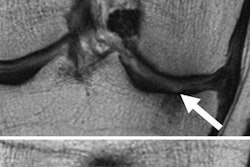

With the help of MRI scans, researchers from the University of Miami observed a link between the duration of time spent in space and a condition known as visual impairment and intracranial pressure (VIIP) syndrome, in which the globe of the eye flattens and the optic nerve can protrude. The condition worsens the longer astronauts stay in space and the effects can linger long after they have returned to Earth.